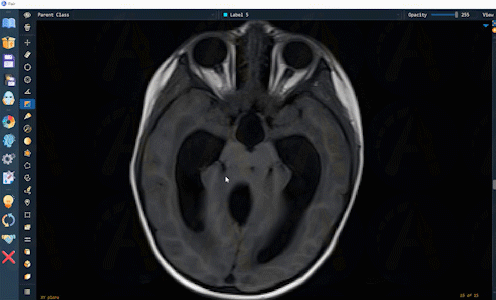

AutoSeg已在CT,MRI,超声,X-ray,PET,扫描电镜,病理,涂片,内窥镜等影像模态的多种解剖结构和病灶上验证和使用。AutoSeg的标注结果可便捷编辑修改,以方便用户微调和快速确认。如下是AutoSeg在多样化的影像和解剖结构上的应用展示: